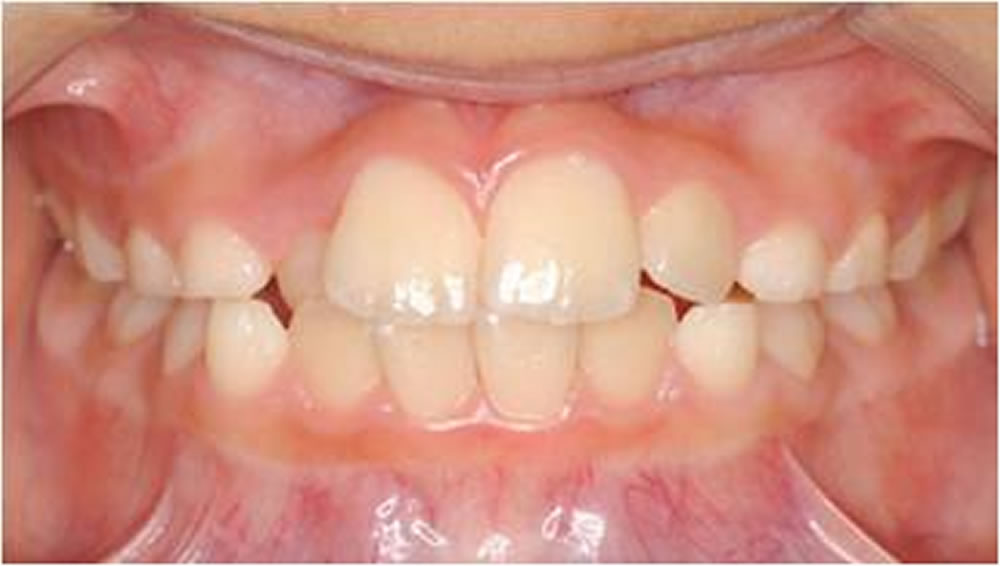

BiVi歯科・矯正歯科で実施した小児矯正の治療例をご紹介

▼当院で実際に行った小児矯正治療の症例をご紹介します。